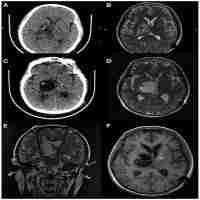

| Abstract | Deep brain stimulation (DBS) is an approved and effective therapy for patients suffering from advanced Parkinson's disease (PD). Several clinical trials have indicated significant motor function improvement in patients undergoing subthalamic nucleus stimulation. This therapy is, rarely, associated with complications, mostly related to infections, seizures or stimulation-induced side effects. We report a case of a 71-year-old man with a 10-year history of PD who underwent bilateral placement of subthalamic nucleus DBS. As a complication, the patient showed subjective postoperative cognitive decline, and subsequent MRI showed peri-lead oedema, which progressed to large cystic cavitation around the leads without indication of infection. The patient received steroid therapy and the cavitations regressed without surgical intervention. |